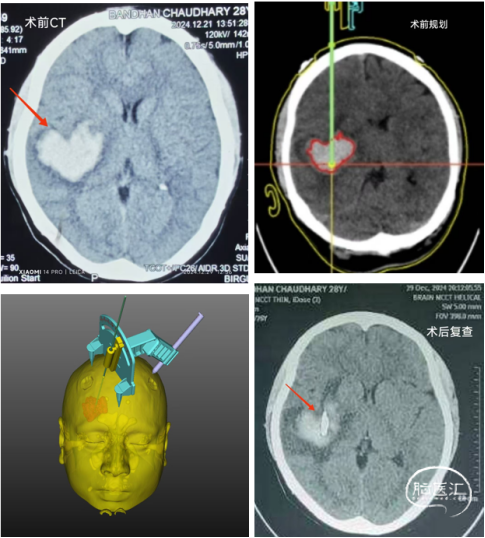

依次是術前CT的心形血腫,術前的平面規(guī)劃和手術設計,以及術后的CT復查,顯示引流管成為精準命中靶心的“丘比特之箭”

今天的手術準備局麻完成,但是患者非常興奮,不停地說話擺頭。和醫(yī)生商量之后決定還是采用靜脈復合麻醉,讓他睡個好覺。丙泊酚一推患者立馬安靜,唐醫(yī)生根據(jù)軟件規(guī)劃完成了導向器三足和穿刺點的頭皮標記,洗手和巡回兩位護士進行消毒鋪單。拉杰夫教授過來打了個招呼就到隔壁手術,就是我們昨天在急診看到的顳葉血腫患者(后來告訴我們確實是動脈瘤)。

其它六七位醫(yī)生聚在我們這邊參觀。這邊的醫(yī)生大多在英國、美國、日本、中國及印度學習過,手術使用的無菌用品質量很好。唐醫(yī)生組裝好導向器和定向顱鉆,上臺不到20分鐘就完成了手術,看到黑紅色的血腫液被緩緩抽出,在場的醫(yī)護都面露笑容。好幾位醫(yī)生表示這樣簡便快捷又高度標準化的技術非常適合尼泊爾。

告別拉杰夫教授后我們去病房探望手術患者,患者完全清醒,感覺癱瘓十余天的左手力量有所恢復,頭痛也明顯減輕。可惜尼泊爾缺尿激酶,全城找到幾只鏈激酶我們又不敢用,要不然血腫清除會更迅速(感覺尼泊爾腦溢血治療的一些微創(chuàng)理念有待普及)。家屬非常高興,邀請我們一起合影。